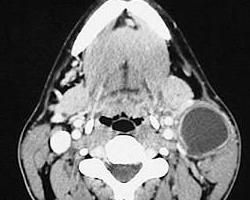

鰓裂瘺管(branchial fistula)為鰓囊、鰓溝相通或鰓溝不消失而生成鰓裂瘺管的外瘺口及全程位於頸部,故又稱頸側瘺管。